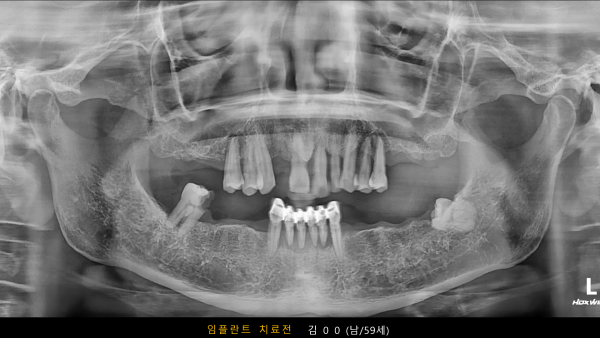

고난도 센터 | 남) 59세